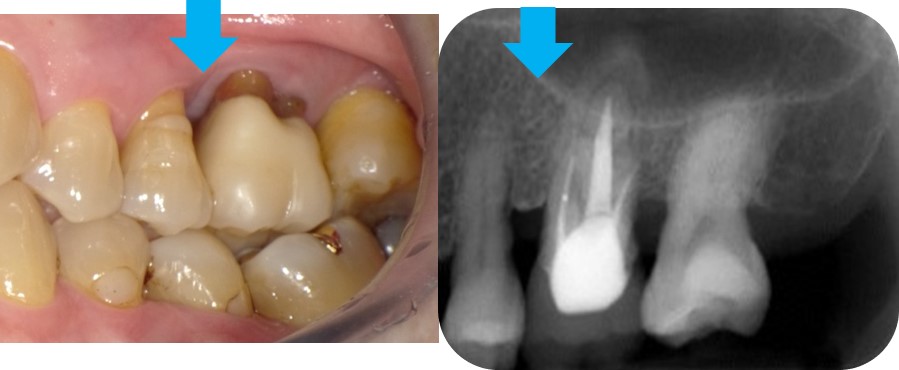

術前写真です。

青矢印が骨吸収している部分です。